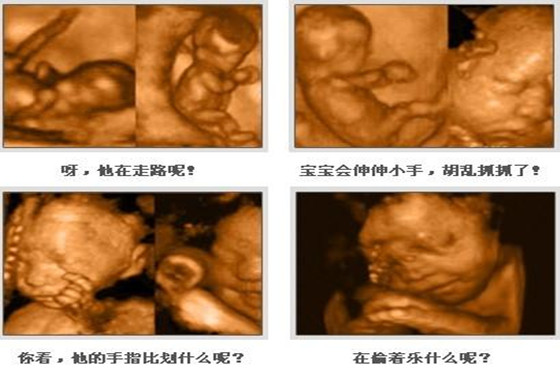

怀孕五个月时胎儿已经长出了头发,眉毛和指甲了,此时胎儿的头部如鸡蛋般大小,他们身上的皮肤也显得不那么透明了,胎儿宝宝在麻麻肚子里可以自由的活动,一些比较调皮的胎儿会毫不留情的在麻麻肚子里“闹腾”,从四维彩超图片可以观察出胎儿的具体动态,他们偶尔会吸吮自己的手指玩耍,好似困了还会打打哈欠,饿了也会做出吞咽动作,有的时候会对麻麻的肚皮“拳打脚踢”,有时也会揉揉自己的眼睛,还有的时候胎儿也会玩弄脐带等等,总之胎儿宝宝在麻麻肚子里面不会那么“乖巧听话”,他们也有自己的一套作息时间,饿了会吃,泛了会睡,无聊时也会玩耍戏弄。